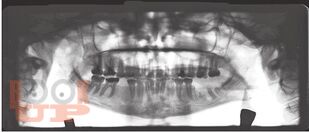

Рождение здорового ребенка зависит во многом от состояния здоровья матери. Ранее перенесенные заболевания, условия труда, прием лекарственных средств до и в течение беременности влияют на развитие плода. Эти и многие другие вопросы еще не нашли должного отражения в учебном процессе как у студентов, так и у врачей. Однако это совершенно не значит, что врач-стоматолог не должен знать их. Многие стоматологические манипуляции у беременных женщин (лечение заболеваний зубов, и их осложнений; заболеваний слизистых оболочек полости рта) проводятся с применением обезболивания, требуют лучевой диагностики и применения лекарственных средств. Своевременно и правильно оказанная помощь, а также профилактика стоматологических заболеваний повысят качество жизни будущей матери и безусловно положительно скажутся на здоровье будущего ребенка. Особенностям лечения и тактике врача-стоматолога посвящена эта работа.